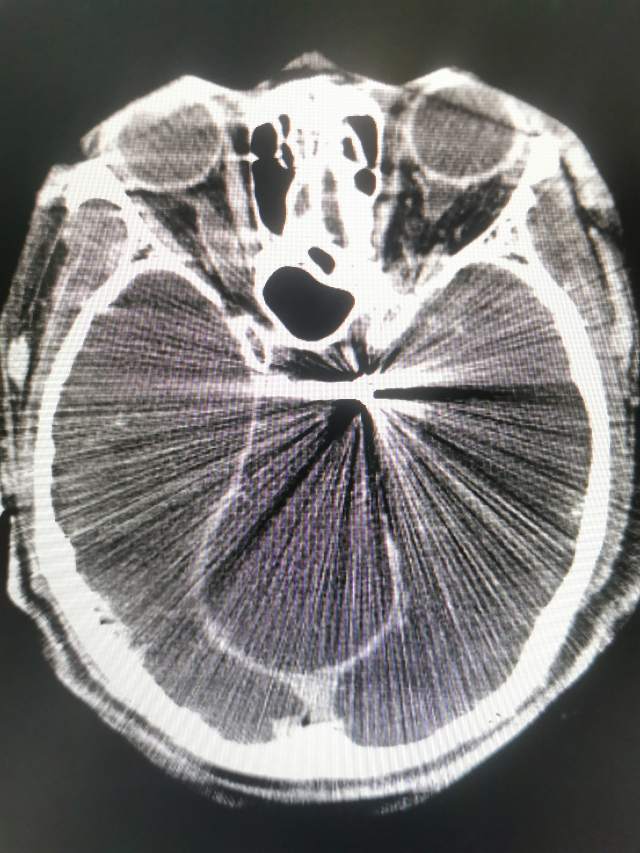

午夜,54岁中年女性,颅内多发动脉瘤破裂出血 ,一个左侧A1动脉瘤,一个左侧胚胎型大脑后动脉瘤(责任动脉瘤;起始部和远端上壁各见一个小泡,后面这个为破裂点;起始部累及粗大胚胎型大脑后动脉),